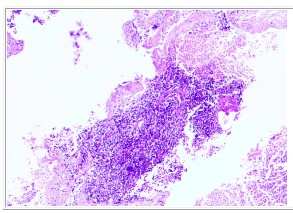

CT引导下右肺肿物穿刺活检病理:不典型类癌(Ki-67 约55%)。

病理检查